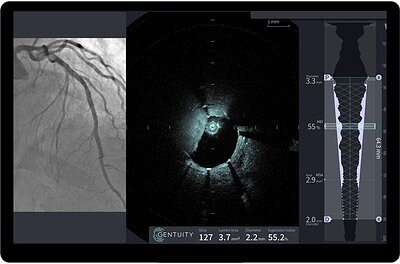

For decades, interventional cardiologists have relied on angiography—a type of X-ray—to guide stent placement. While effective, angiography provides a two-dimensional shadow of the artery, leaving room for ambiguity. Intravascular imaging, which places a miniature camera inside the vessel, offers a far more detailed, cross-sectional view. Gentuity’s HF-OCT technology represents the cutting edge of this field.

Optical Coherence Tomography uses light to create high-resolution images, providing detail at a microscopic level that is superior to older intravascular ultrasound (IVUS) technology. This allows physicians to precisely measure vessel dimensions, characterize plaque composition (e.g., fibrous, calcified, or lipid-rich), and confirm that a stent is properly sized, positioned, and fully expanded against the artery wall. Clinical evidence has consistently shown that OCT-guided PCIs lead to better outcomes, including a reduced risk of stent failure and major adverse cardiovascular events.

What sets Gentuity's system apart is its technical innovation. The Vis-Rx® PRIME Micro-Imaging Catheter is touted as the world's smallest, with a diameter of just 1.8 French (approximately 0.6 mm). This ultra-low profile is 55% smaller than leading competitors, enabling it to navigate and image extremely narrow and complex lesions that were previously inaccessible. Furthermore, the system can perform a rapid 100-millimeter scan of an artery in a single, one-second pullback, providing a comprehensive view for real-time decision-making without significantly extending procedure time.